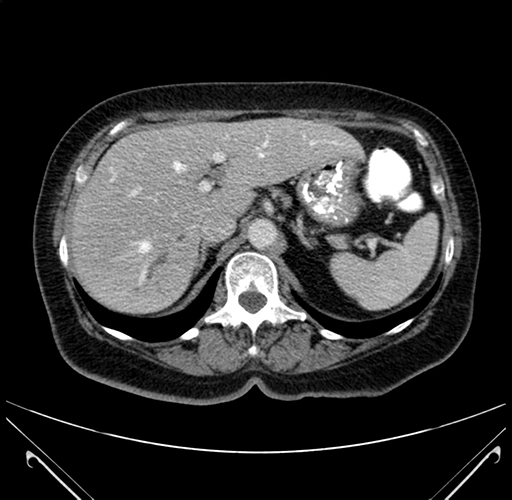

Axial Venous